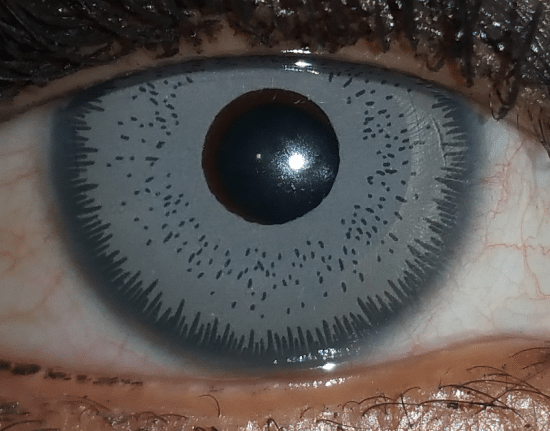

Prothèse d’iris artificiel destinées à changer la couleur d’yeux initialement marrons. A faible distance ou après grossissement, la texture et le motif diffère grandement de celui d’un iris naturellement bleu (implant « ice gray »). Ici, la prothèse est teintée en bleu (elle absorbe toutes les couleurs du spectre visible sauf le bleu), alors que les yeux qui sont naturellement bleus possèdent un iris peu pigmenté qui induit la diffusion accrue de la lumière bleue.